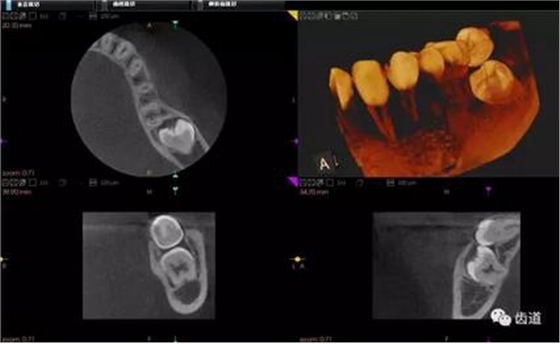

1、下頜骨種植牙前測(cè)量準(zhǔn)備影像

2、上頜骨種植牙前準(zhǔn)備影像

三)種植修復(fù)

CBCT在牙種植修復(fù)中的應(yīng)用。種植前利用CBCT對(duì)患者的牙床進(jìn)行檢查,可精準(zhǔn)判斷牙槽骨的寬度、厚度及高度、骨的密度、重要的顏面神經(jīng)、血管和鼻竇位置等。臨床醫(yī)生不僅可以在計(jì)算機(jī)直觀的看到牙槽骨的立體影像,還可以切換不同的視角來(lái)觀察硬組織之間的位置關(guān)系,在手術(shù)方案中避開危險(xiǎn)區(qū)域,保證手術(shù)的安全性。臨床醫(yī)生還可以利用CT數(shù)據(jù)進(jìn)行數(shù)字模型重建,配合軟件預(yù)先做好手術(shù)模板,使種植手術(shù)更安全快捷,避免在種植手術(shù)過(guò)程中不慎破壞神經(jīng)、鼻竇等解剖結(jié)構(gòu),導(dǎo)致顏面神經(jīng)麻痹、鼻竇炎等并發(fā)癥的發(fā)生。